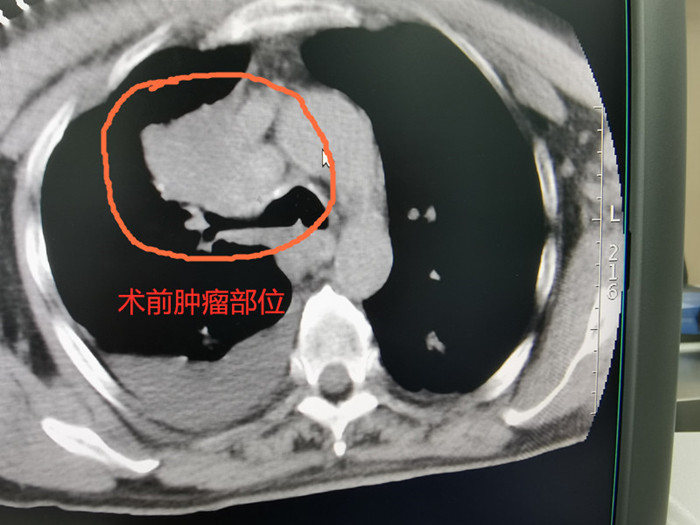

術前CT

68歲的吳老伯因確診右上肺鱗癌收治入院,腫瘤侵犯胸膜及上腔靜脈,失去手術根治切除的機會,放化療效果也不理想。經(jīng)過多次討論,腫瘤放療團隊決定為他實施共面模板引導下放射性粒子植入術。